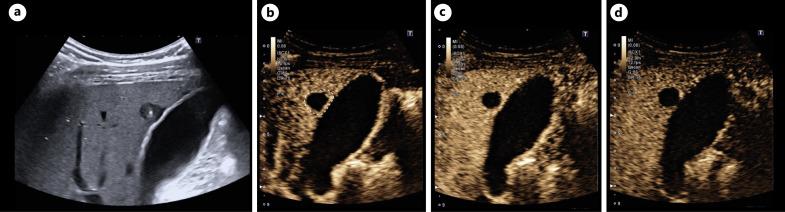

The use of the ultrasound classification developed by us and the use of contrast-enhanced ultrasound (CEUS) helps make the diagnosis faster and better. Without CEUS, the hemangioma-like pattern and the metastasis-like pattern in particular cannot be diagnosed with certainty. The limitations of ultrasound diagnostics on the patient side, in terms of examiner experience and equipment, remain.

使用我们开发的超声分类方法以及对比增强超声(CEUS)有助于更快、更好地进行诊断。没有CEUS,特别是血管瘤样模式和转移样模式无法确诊。在患者方面,超声诊断在检查者经验和设备方面的局限性仍然存在。